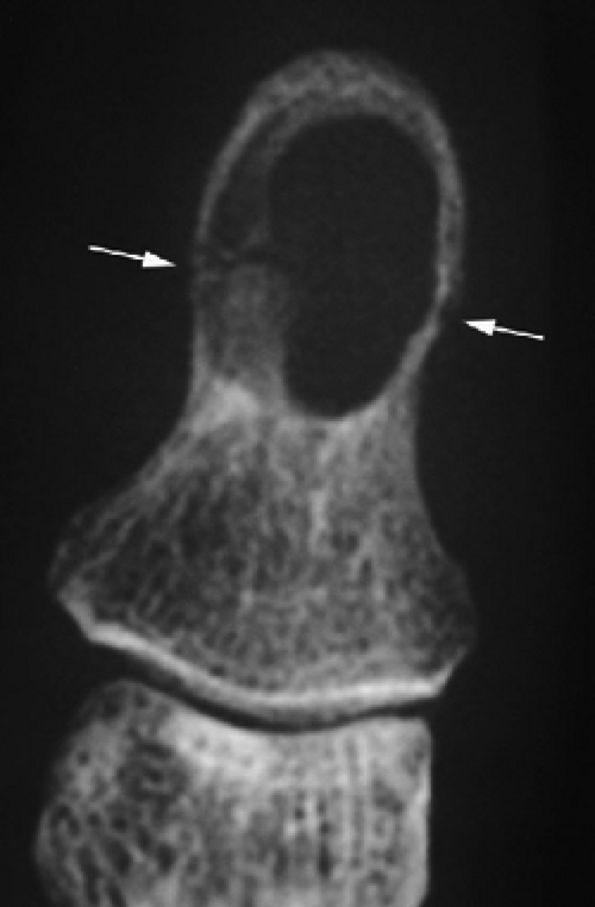

FIGURE 11.128 ● Vascular-type glomus tumor (asterisk) of the nail bed with the most common signal characteristics. (A) Axial T2-weighted image. T1-weighted images before (B) and after (C) injection of gadolinium. (D) MR angiogram. The tumor is located on the midline with an underlying bone erosion (arrowheads). The signal is high on T2-weighted images and slightly high on T1-weighted images. There is strong post-contrast enhancement on T1-weighted images and MR angiography.